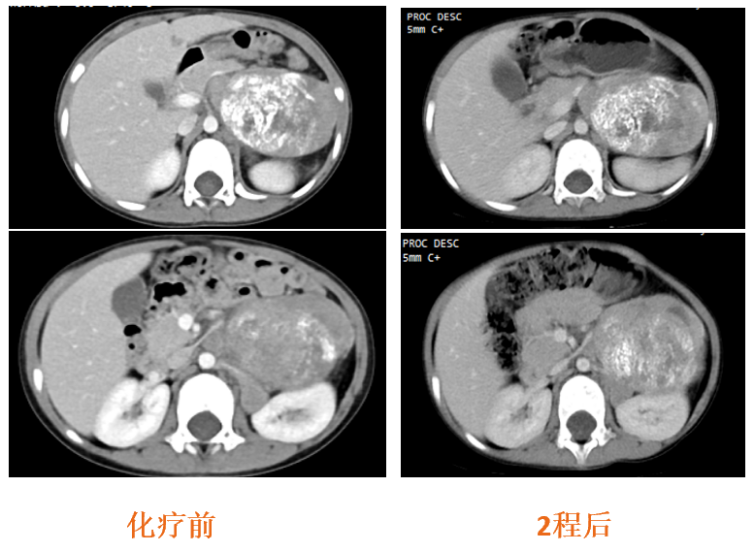

2024-1-6、2024-1-27

在外院行CAV/VIP方案化疗2程,化疗后腹膜后病灶稳定(图5),疗效SD;胸骨骨髓涂片未见肿瘤(CR)。

图5:治疗前及2程化疗后CT